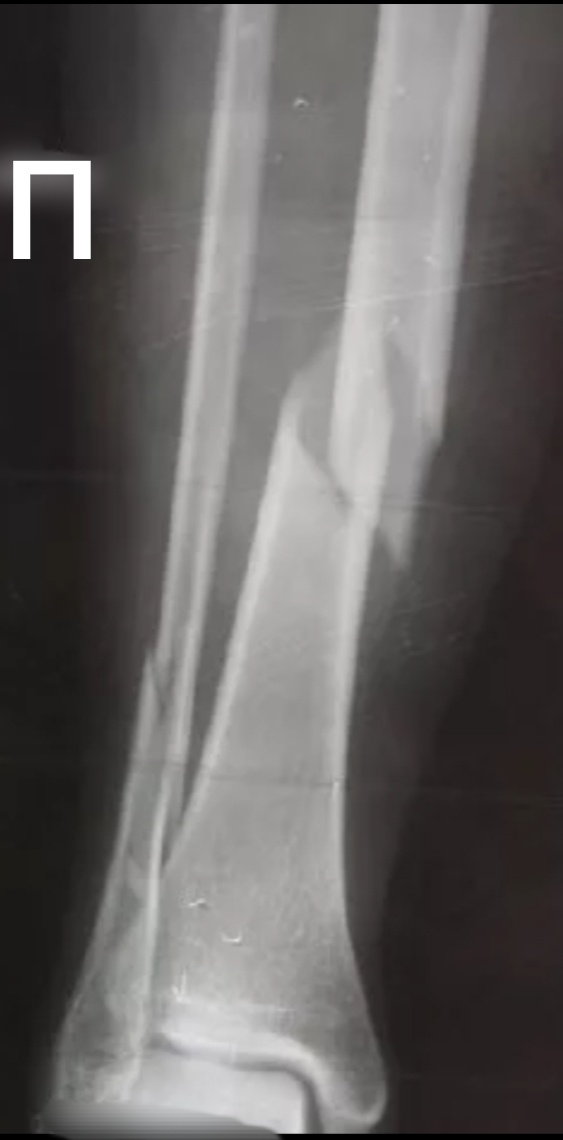

Пока берут анализ, внесла в базы пациента, назначена голень и легкие.

- Где ж вы ногу сломали?- поинтересовалась я у пациента, завозя каталку.

- Не поверите, бревно на ногу упало.

- Вы лесоруб?- недоверчиво переспросила я

- Да , на лесопилке работаю.

- О, а как же вы так?- ставлю каталку под луч.- Снимайте футболку.

– Да...- махнул рукой пациент.- Если честно, то сам виноват, конкретно технику безопасности нарушил.

- Ложитесь, снимок сделаем. Не дышать!

Сняла легкие, нужно голень теперь.

- Большое бревно- то было?

– Приличное, береза, метров 15.

👀

- Ничего себе( не то слово)!!!

- Да, уже назад не вернешь, скорая сразу сказала, что перелом.

– Так а как тогда страховку оформлять?

– Никак, я ж говорю, технику безопасности конкретно нарушил.

- Так, можно сказать, вам повезло?

- Я считаю, что да.

Снимок.

-2

А я вспомнила тоже одного лесоруба, только ему дерево упало на бедренную кость и на берцовки тоже. Артерии перебило, ампутировали ногу в итоге, не смогли восстановить кровоток.

Тут хоть не так все кисло.